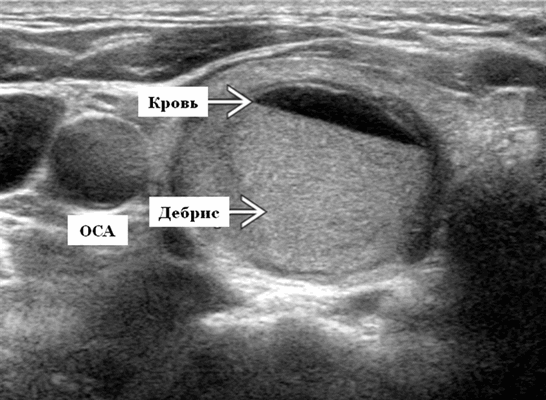

- Четко выраженный, преимущественно кистозный узел щитовидной железы, содержащий продукты крови различной давности ± уровень жидкости

- УЗИ: преимущественно кистозный узел щитовидной железы с эхогенным детритом ± уровень жидкости, бессосудистые септы или бессосудистый солидный компонент. ТАБ неизменно дает измененную кровь

- При проведении УЗИ определяется четко выраженный, преимущественно кистозный узел щитовидной железы, содержащий продукты крови различного возраста с осадком и уровнем жидкости и нет солидного компонента. Киста ограничена капсулой щитовидной железы и нет местного вторжения за ее пределы. Фоновый многоузловой зоб (МУЗ) довольно распространен. Если киста большая, то возможен масс-эффект из-за воздействия на трахею, общую сонную артерию и внутреннюю яремную вену

- Ультразвуковое исследование в оттенках серого. Преимущественно кистозный узел щитовидной железы с мобильным эхогенным включением ± уровень жидкости. Тонкая или толстая перегородка / септы ± эхогенный, солидный компонент в зависимой или независимой области представляет сгусток крови, мягкий по консистенции при ТАБ (аваскулярный по допплеру).